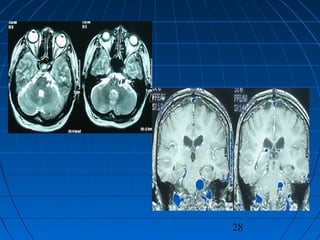

 HP: 53 yaşında kadın hastaHP: 53 yaşında kadın hasta

 Akut, şiddetli başağrısıAkut, şiddetli başağrısı (şiddetli, son 24(şiddetli, son 24

saat içinde)saat içinde)

 GKS 14, Nörodefisit yok (WFNSGKS 14, Nörodefisit yok (WFNS

grade 2)grade 2)

 Fisher grade IIIFisher grade III

CERRAHİCERRAHİ

 Sol suboksipital retrosigmoidSol suboksipital retrosigmoid

yaklaşımyaklaşım

 Anevrizma kliplendiAnevrizma kliplendi